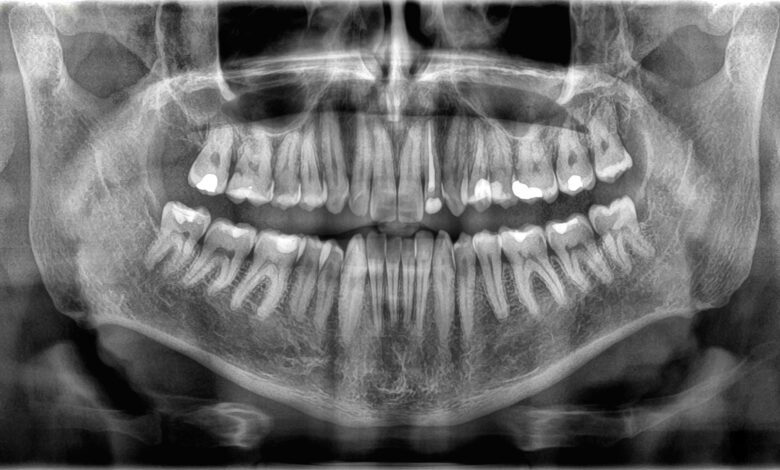

Protože kosti a zuby vykonávají různé funkce, jsou také jinak stavěny. Vnější struktura zubů je tzv smalttenká vrstva mineralizované tkáně. Sklovina je nejtvrdší látka v těle – vlastnost, kterou získává ze zaseknutých krystalů vyrobených ze sloučeniny vápníku a fosfátu.

Pod sklovinou leží dentin, typ mineralizované tkáně, která je o něco měkčí než sklovina, ale stále tvrdá. Dentin tvoří většinu struktury zubu a obsahuje malé trubičky, které drží krevní cévy a nervová zakončení. Jádro zubu je tvořeno rosolovitou látkou zvanou dřeň, která obsahuje více krevních cév, které poskytují živiny zubu a nervům, které řídí cit v zubu.

Kosti jsou pokryty velmi tenkou, tuhou vnější vrstvou nazývanou periosteum, ve které jsou uloženy krevní cévy a nervy nezbytné pro růst a hojení tkáně. Další vrstva je složena z odolné kompaktní kostní tkáně. Vnitřek kosti obsahuje spongiózní tkáň, houbovitou hmotu s drobnými otvory, které obsahují kostní dřeň, kde se tvoří nové krvinky.